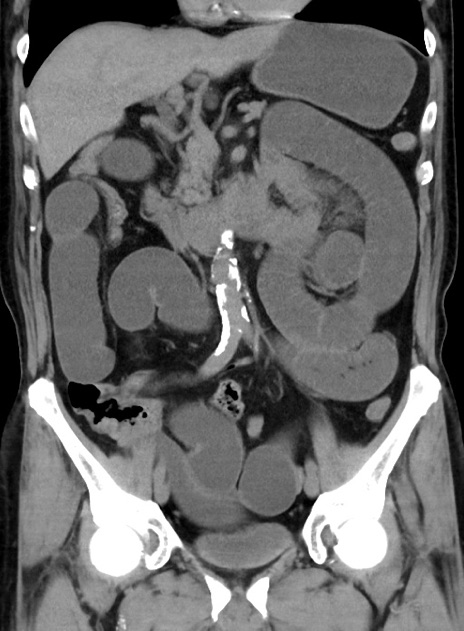

症例38(冠状断像)

【症例】70歳代 男性

【主訴】腹痛・嘔吐

【現病歴】昨晩より、嘔吐・腹痛あり。今朝になっても嘔吐あり。来院。

【既往歴】心臓バイパス手術、開腹胆摘、腸閉塞

【身体所見】BP 107/71mmHg、HR 116/min、腹部:平坦、軟、下腹部に軽度圧痛あり。反跳痛なし。

【データ】WBC 15100、CRP 0.32

横断像